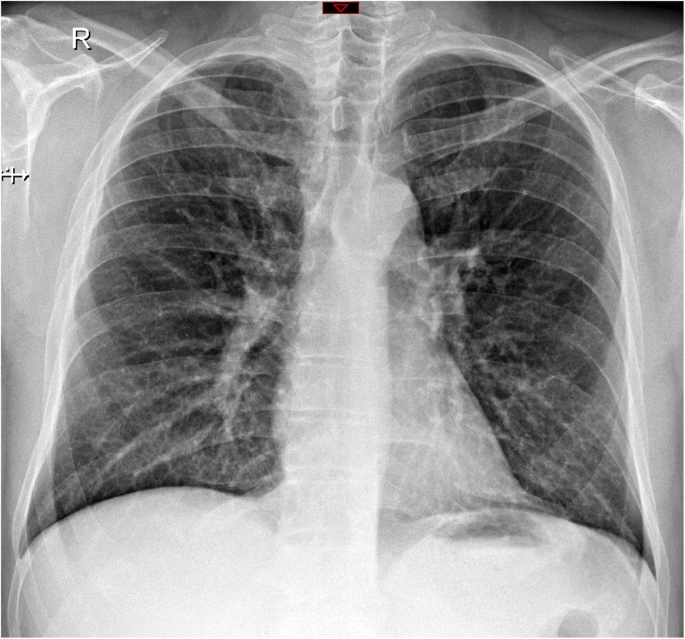

- Matglasforandringer (Ground-Glass Opacities - GGO): Dette er det hyppigste fund. På en CT-scanning ser det ud som tågede eller slørede områder i lungerne, hvor man stadig svagt kan ane de underliggende blodkar og luftveje. Disse forandringer indikerer en delvis fyldning af lungeblærerne (alveolerne) med væske, celler eller andet materiale, hvilket reducerer luftindholdet. Matglasforandringer kan være spredt i små pletter eller dække større, sammenhængende områder.

- Konsolidering: Dette refererer til områder i lungen, hvor lungeblærerne er helt fyldt med inflammatorisk materiale (væske, pus, blod), hvilket gør lungevævet tæt og solidt. På en CT-scanning fremstår konsolidering som helt hvide, uigennemsigtige områder, hvor de normale lungestrukturer ikke længere kan ses. Dette er ofte et tegn på en mere alvorlig lungebetændelse.

- Kombination af matglas og konsolidering: Det er meget almindeligt at se en blanding af begge mønstre. Ofte kan et område starte som matglas og udvikle sig til konsolidering, efterhånden som inflammationen forværres.

- Fordeling i lungerne: Mønstrene ved influenza har ofte en tendens til at være placeret peribronkovaskulært (omkring luftvejene og blodkarrene) og subpleuralt (lige under lungehinden). Fordelingen er typisk multifokal og plettet, hvilket betyder, at den optræder flere steder i begge lunger.

Et af de mest overraskende og vigtige punkter er, at en CT-scanning kan være fuldstændig normal hos en patient med en bekræftet influenza-infektion. Studier har vist, at dette kan være tilfældet i op til halvdelen af patienterne, især dem med mildere symptomer, hvor infektionen primært er begrænset til de øvre luftveje. En normal CT-scanning udelukker altså ikke influenza, men det indikerer, at der ikke er udviklet en signifikant lungebetændelse, som er synlig på scanningen. Dette understreger, at diagnosen altid skal baseres på en kombination af symptomer, klinisk undersøgelse og laboratorietests (f.eks. en podning).

Et almindeligt røntgenbillede er ofte den første undersøgelse, men det er mindre følsomt end en CT-scanning. Milde forandringer som lette matglasforandringer kan være usynlige på et røntgenbillede. En CT-scanning giver et langt mere detaljeret billede af forandringernes type, placering og omfang.